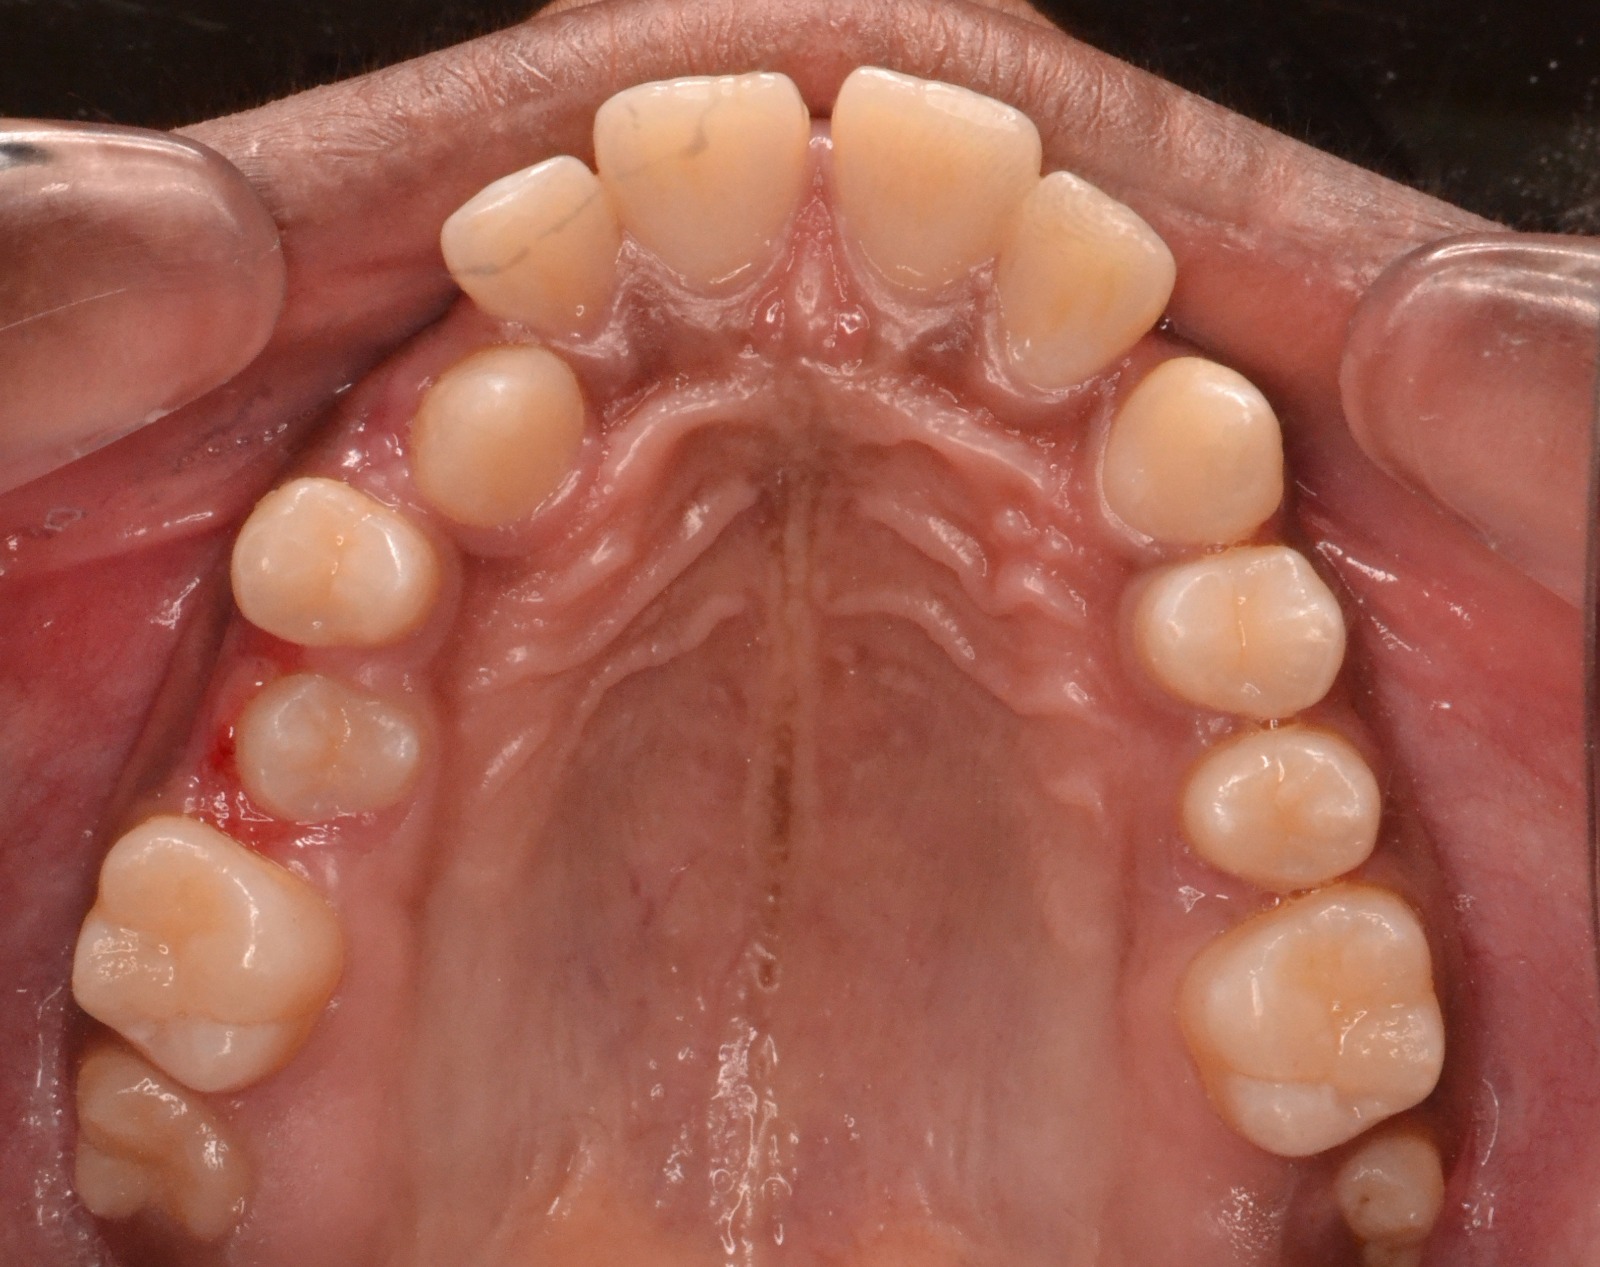

After/Before

See stunning smile transformation before and after

Before After